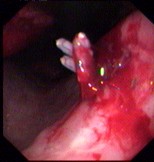

在出血上方注射硬化劑 | 胃鏡下鉗夾止血 |

在出血上方注射硬化劑

胃鏡下鉗夾止血